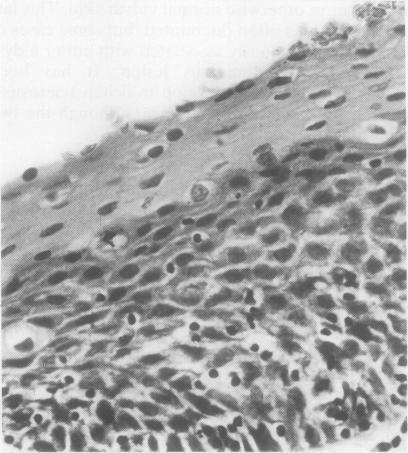

The pathological, cytological, and clinical features of vulvar intraepithelial neoplasia (VIN) are described. The rate of progression of VIN III to an invasive carcinoma is very low and spontaneous regression can occur. These features prevent the drawing of a direct analogy between vulvar and cervical intraepithelial neoplasia. The concept of microinvasive carcinoma of the vulva is discussed, and it is concluded that no satisfactory definition of this entity has been achieved.

本文描述了外阴上皮内瘤变(VIN)的病理、细胞学及临床特征。VIN III进展为浸润性癌的发生率很低,且可发生自发消退。这些特征使得外阴上皮内瘤变与宫颈上皮内瘤变无法直接进行类比。文中对外阴微浸润癌的概念进行了讨论,得出的结论是尚未对该实体达成令人满意的定义。